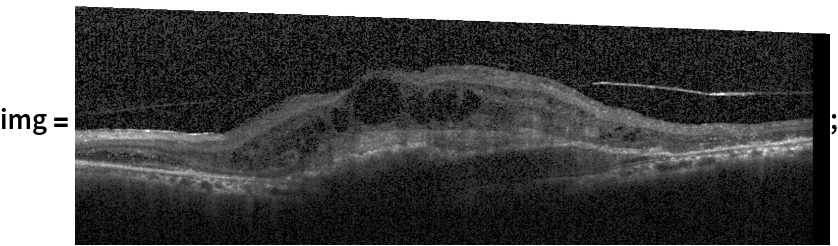

Classify a retinal image:

In[6]:=

(* Evaluate this cell to get the example input *) CloudGet["https://www.wolframcloud.com/obj/678a4622-981f-43e9-a76f-e102c0a9e0a3"]

In[7]:=

In[8]:=

pred = NetModel["Optic-Net Classifier for Retinal Diseases"][img]